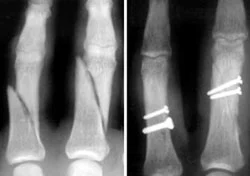

Metacarpal Fractures

- Careful about rotational malalignment

- Check rotation by flexing the fingers

Finger malrotation

- Undisplaced / or only one MC

- Treatment by cast / or splint

- Displaced / Rotated / Multiple

- Treated by internal fixation (screws / plates / wires)